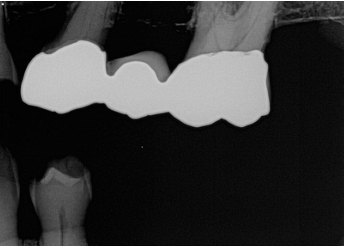

What is the problem with this FIXER CUT-OFF X-ray?

Appears with straight black border, Unfixed portion of film caused by low level of fixer

How would you resolve this FIXER CUT-OFF X-ray?

Check fixer level before processing and add solution if needed